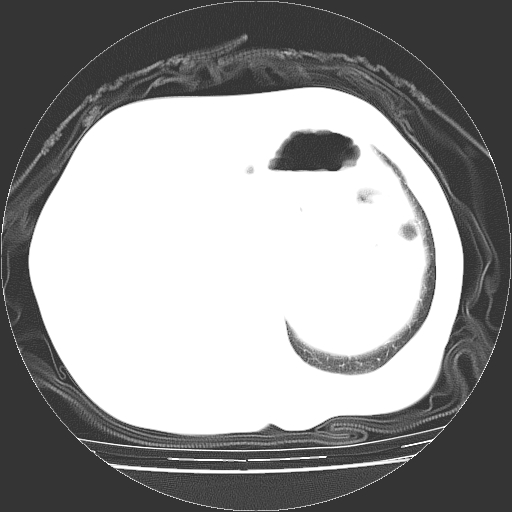

标题: CT23991:女,72岁,咳嗽、憋气一周。 [打印本页]

女,72岁,咳嗽、憋气一周,十年前曾患肺结核及胸膜结核。

右侧毁损肺,右侧纵隔疝,左肺代偿!

右侧肺硬变,左肺代偿气肿。

右侧肺毁损,左肺代偿性肺气肿,纵隔疝。